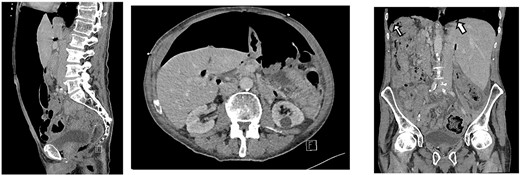

CT scan on initial presentation showing pneumoperitoneum without obvious cause. Sagittal, axial, coronal views. Arrows show pockets of free intraperitoneal air

On presentation, his temperature was 37.8°C, and he was hypotensive at 100/45 mmHg and tachypneic with a respiratory rate of 22. He was in moderate respiratory distress and was placed on 2 L oxygen via nasal prongs. On abdominal examination, mild distension was noted with lower abdominal tenderness with rebound tenderness and guarding in the right lower quadrant. He had normal leukocytes of 5 × 109 /L (N: 4.0–11 × 109/L) and lactate was normal at 1.6 mmol/L (N: 0.5–2.2 mmol/L). X-ray chest showed free air under the diaphragm suggestive of pneumoperitoneum (Fig. 1). A CT abdomen was performed showing large-volume free air suggestive of a viscous perforation and moderate volume of free fluid in the abdomen (Fig. 2). The site of perforation was not confidently established on the study. There was generalized oedema of the right side of the colon with multiple loops of dilated small bowel. His Physiological and Operative Severity Score for enumeration of Mortality and Morbidity (POSSUM) score would be 81% predicted mortality and 98.8% predicted morbidity if he were to undergo an emergent laparotomy operation. Family discussion was made, and he decided not to proceed with operative management. He was managed conservatively with piperacillin-tazobactam and decompressed with nasogastric tube insertion. As the days progressed, his abdomen became increasingly distended and tympanic, but not peritonitic. We repeated a CT chest and abdomen three days after initial admission and it was reported he had tension pneumoperitoneum (Fig. 3). CT with oral contrast was also performed to exclude an upper GI perforation.